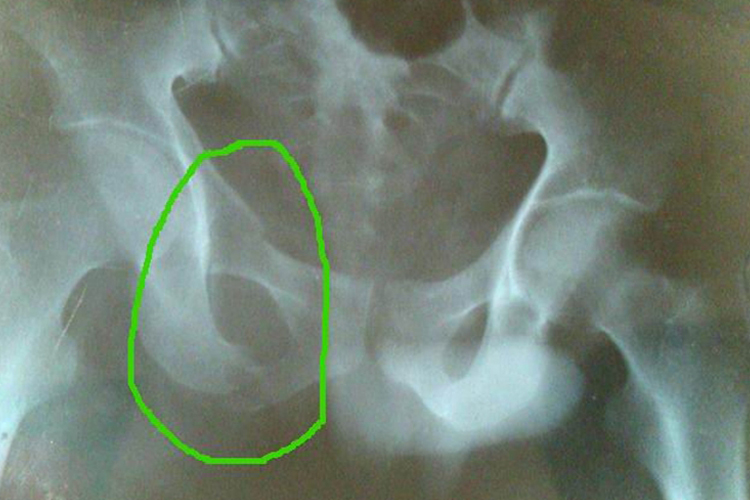

右耻骨下支骨折通常是直接暴力损伤所致,如车祸、重力撞击等,患者有局部疼痛、肿胀、淤斑等症状,需由专业医师复位治疗。

右耻骨下支骨折由于耻骨弓骨性结构破坏,骨皮质连续中断,会导致骨折碎片移位,而外力和移位的骨折片可损伤尿道、膀胱或直肠,其中以尿道损伤最为多见。

右耻骨下支骨折后会有局部疼痛、肿胀等表现,会阴部、腹股沟部或腰部可出现皮下淤斑,导致患者下肢活动和翻身困难,患侧下肢可有短缩畸形。